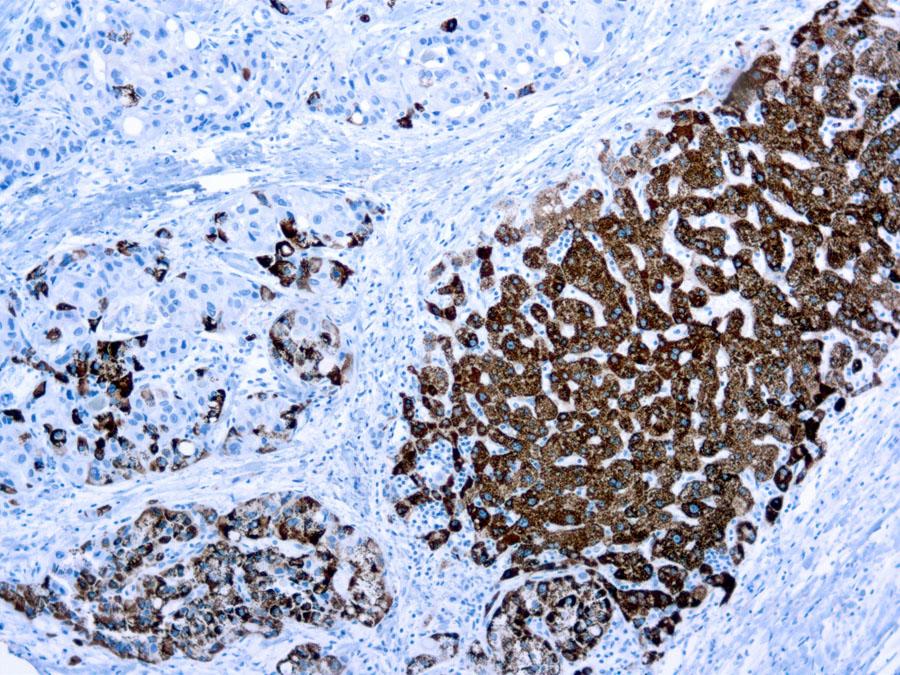

Figure 1 : Formalin fixed paraffin embedded liver stained with Hepatocyte Specific Antigen antibody ( 10-11530).

Hepatoblastoma is the most common primary tumor of the liver in children. The use of specific hepatocyte markers and also of fetoprotein or carcinoembryonic antigen are useful for the identification of normal and malignant fetal hepatocytes. This antibody recognizes an uncharacterized antigen present in both adults and fetal normal hepatocytes to produce a distinct granular cytoplasmic staining. This antibody stains majority of hepatocellular carcinomas.